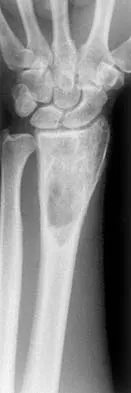

Figures 48a and 48b show the elbow radiographs of a 5-year-old boy who fell from a tree after dinner. Examination reveals that he is unable to extend his wrist. Management should consist of immediate

Explanation